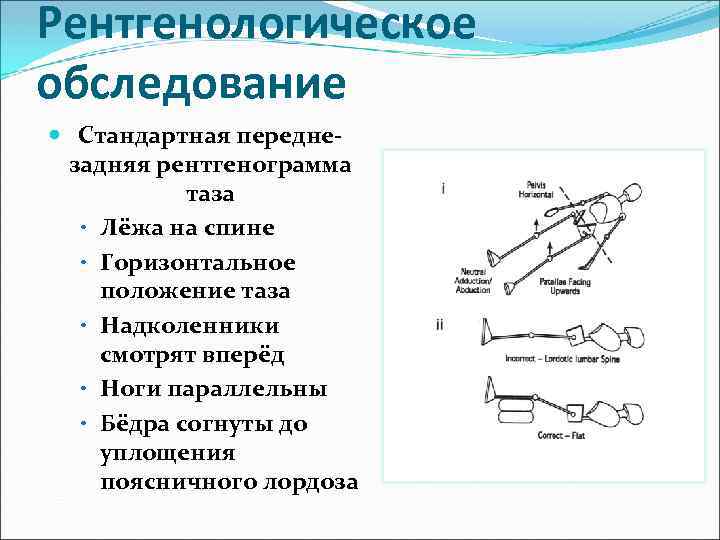

Рентгенологическое обследование Стандартная переднезадняя рентгенограмма таза • Лёжа на спине • Горизонтальное положение таза • Надколенники смотрят вперёд • Ноги параллельны • Бёдра согнуты до уплощения поясничного лордоза